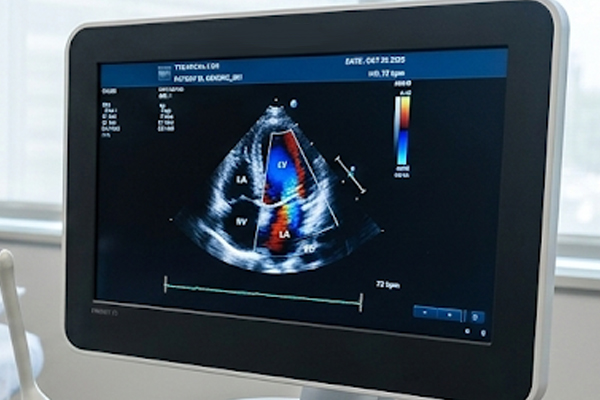

ECOCARDIOGRAMA TRANSTORÁCICO

Outros nomes/mesmo exame: Ecocardiograma bidimensional com doppler e fluxo em cores, ecodopplercardiograma, ecocardiograma bidimensional com doppler, ecocardiograma-color doppler.

É um exame relacionado ao estudo anatômico e funcional do coração utilizando o ultrassom.

Estudo das cavidades cardíacas, dimensões, análise das funções ventriculares, cálculo da fração de ejeção, estudo das valvas cardíacas, análise dos fluxos sanguíneos intra cardíacos, análise parcial dos vasos da base (aorta e tronco da artéria pulmonar) e pericárdio.

O ecocardiograma transtorácico é um exame indolor e praticamente sem riscos sendo realizado sem nenhum preparo específico com o paciente acordado (Não se utiliza sedativos ou anestésicos).  O paciente fica em posição deitada e o médico utilizará uma sonda com gel na região anterior do tórax para estudar o coração.